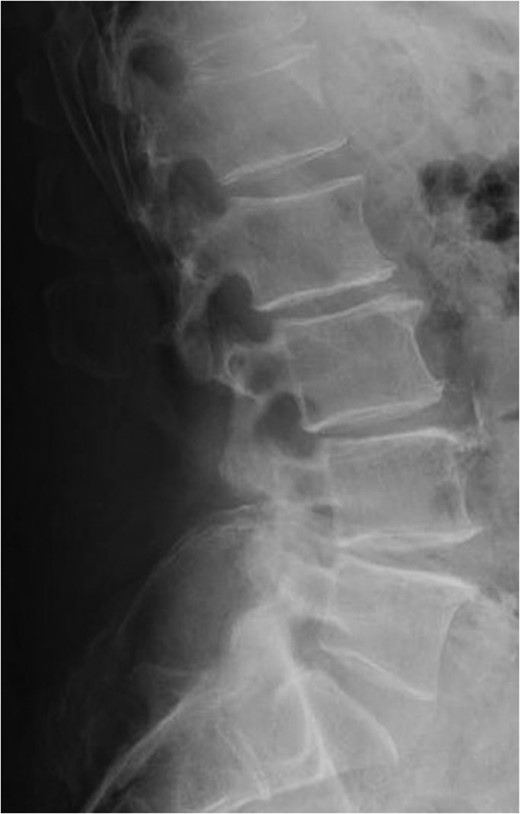

Standing neutral lateral lumbar radiograph obtained 17 months following the patient's L3–S1 laminectomy. The patient is now dealing with a Grade 1 anterolisthesis of L4 on L5, with a mild degree of retrolisthesis at each of the cranial levels depicted.